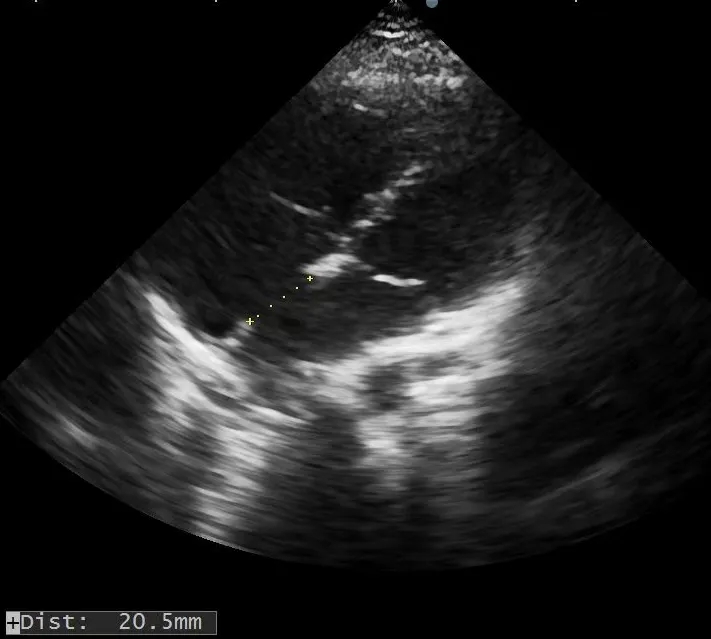

术前复测

多切面测量房间隔缺损直径为

20.5mm×22.0mm×21.6mm